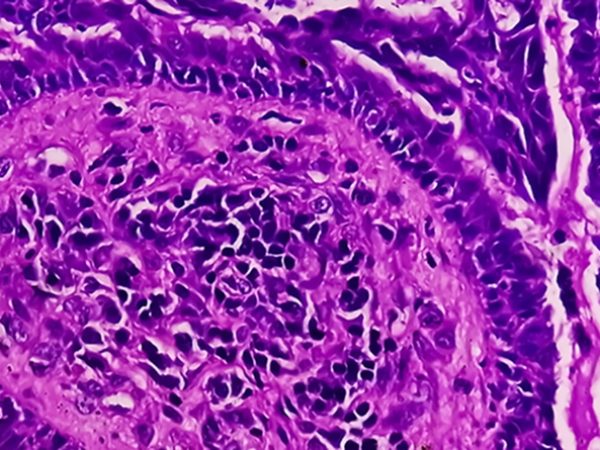

Uterine Sarcoma

When cancer forms in the uterine muscles or in tissues that support the uterus, it is known as uterine sarcoma. This is different from endometrial cancer, in which cancer cells form inside the lining of the uterus. Uterine sarcoma is very rare and accounts for less than 1% of gynecologic cancers, according to the National Cancer Institute.